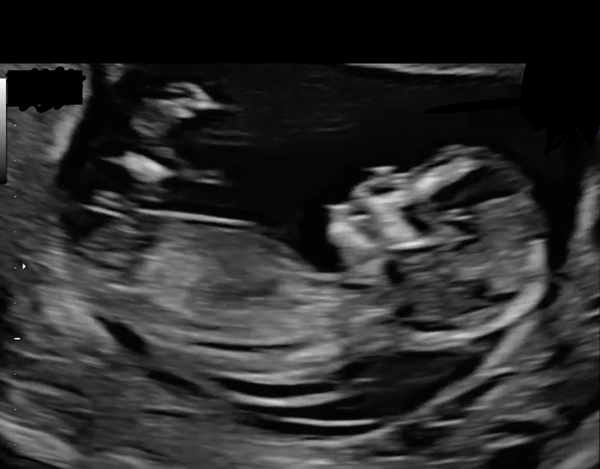

I just turned 35, but got pregnant at 34 (much appreciated baba after fertility troubles). We had a private scan at 10 weeks and it showed increased NT (3mm) but still within a norm. This however left us very concerned for our baby, as I did a lot of reading and knew what this could mean. The 2.5 week for the 12 weeks scan was an agony. At our 12 weeks scan (I was actually 13 weeks 0 days) NT has sadly increased to 6.6mm, meaning it was very high :(

I had a CVS yesterday and it was confirmed that in my case due to correct levels of PAPP-a and HCG Down Syndrome is very unlikely. My test was send for detailed chromosomes check for something more rare though... So we have 2 weeks wait now. On the other hand the baby looks anatomically normal, there is nothing else wrong, baby is slightly bigger than my dates and it's moving a lot, a little wriggler they called him/her 🥰 So it is all a good sign too. Praying it comes clear, nonetheless we're so worried😥

Hi @Bibbidiboo. Your scan picture doesn't look different to mine. Your baby is beautiful. I'm sorry you didn't get to speak to someone more empathetic. Can't believe someone would say baby would be gone, before getting any results. After my 12 weeks scan I spoke to a lovely midwife. She said she recently had a patient with NT 9mm and she ended up having a completely healthy baby. So don't give up your hope.

Are you in US? I'm in UK. Perhaps things are a little different. Here CVS is as much useful diagnostic test as Amnio. And because Amnio can be done from 15 weeks I decided not to wait and have CVS at 13 weeks and get the results faster. I couldn't bear to wait and stress for longer. Also at 12 weeks baby's heart is the size of half of our fingernail so way to small to examine. Even at 13 weeks at Fetal Medicine Unit, where we were referred after high NT, they could only check the blood flow in the heart, and not heart itself, because it was still too small. Detailed heart scan can be done from 16 weeks. But great that they said things look good otherwise. Have they found anything else worrying? I encourage you to do the Amnio and get some answers.

Anatomically there was nothing else wrong, the baby looked perfectly fine: brain, skull, abdomen, stomach, hands and feet, blood flow. Baby is also moving so much every time we have a scan. It is heartbreaking to even think of TFMR when I see my baby moving so lively :( There was no mention of cystic hygroma in our case. But this is what I found on the Internet: If your baby has normal chromosomes and the cystic hygroma disappears by 20 weeks of pregnancy, the outcome will probably be good. If the cystic hygroma does not resolve by 20 weeks, the chance of a healthy outcome decreases to two to nine percent. So everything comes down to chromosomal abnormalities. Search CVS microarray. This is what our doctor opted for us and it shows full chromosomal conditions, same as Amnio. Perhaps microarray is not funded in Australia, hence it's comparable to NIPT and Amnio is the only full diagnostic test? How far along are you? Hopefully you can do Amnio as soon as possible and get your results x

The thought of TFMR is just more than I can bear. The ultrasound was just so much more detailed then I expected - we could literally see the baby opening their mouth, sticking out their tongue and drinking. Everything else on the scan was just perfect and developing normally.